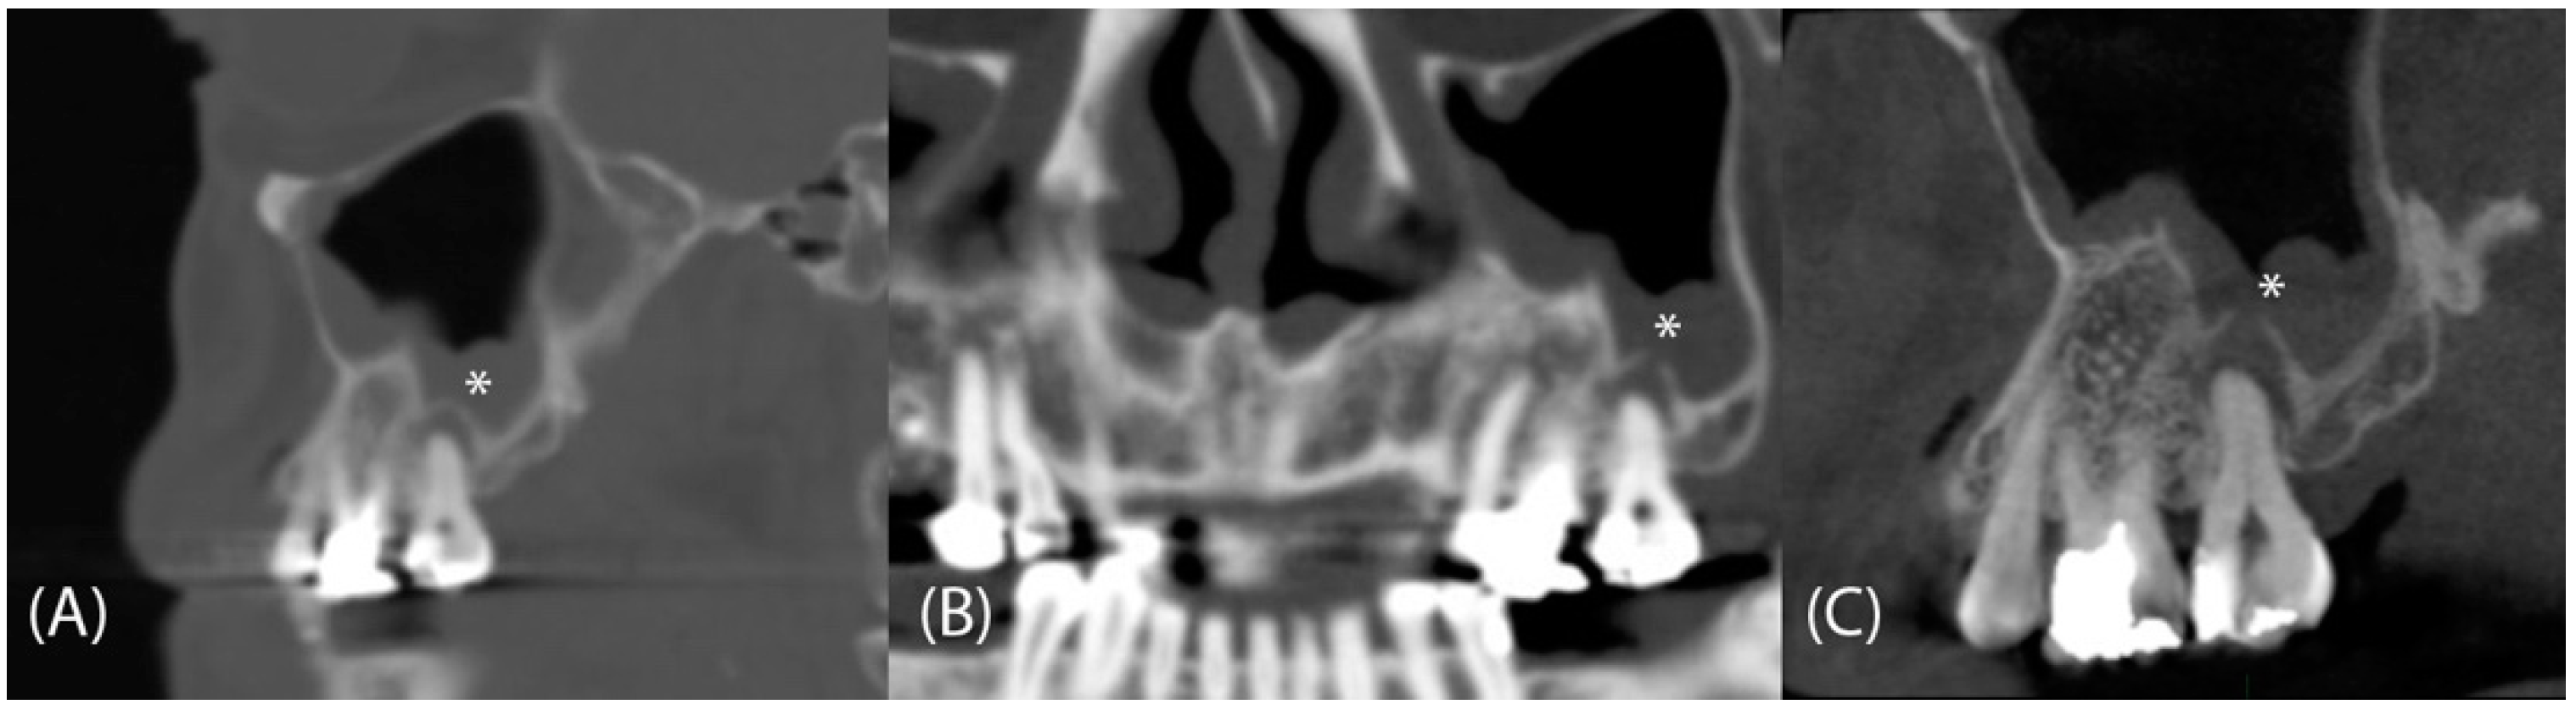

1. Introduction

2. Materials and Methods

2.2. Assessment of Dental Pathologies and Sinus Conditions